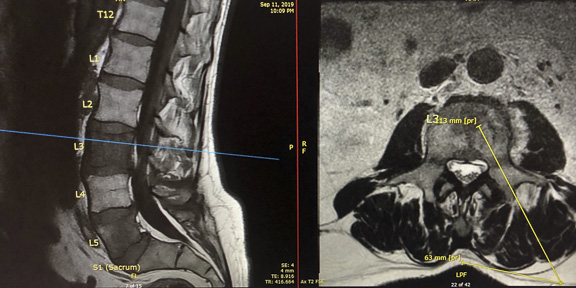

Dr. Massari, a member of the UMass Neurointerventional Radiology Group performed a transpedicular lumbar vertebra biopsy on a patient referred by a local practitioner. Pictured is the radiology team from left to right: Lisa Laprade, procedural technician, Jayne Roose, RN, Kalyn Dhroso, PA, Francesco Massari MD, Amin Chaoui, MD, Danielle McHugh RT CT.